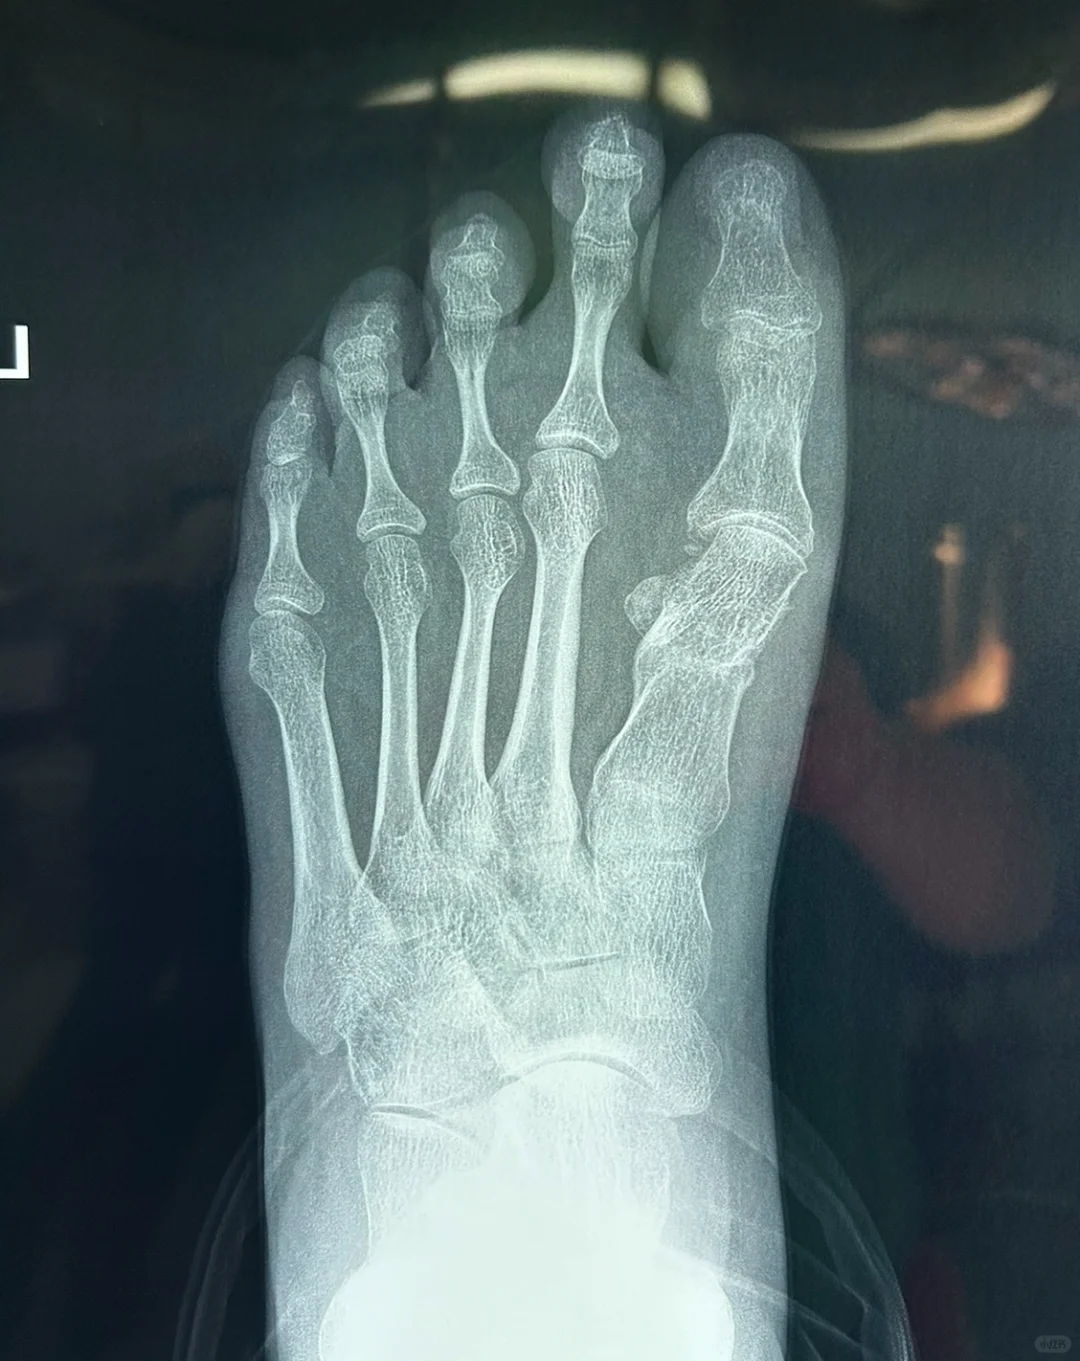

微创术后有一种特殊畸形,就是图中的反旋转畸形。

本来拇外翻畸形就是跖骨向内,也就是向脚心方向出现旋转,我们的手术本来也应该断骨后向二趾方向旋转回来即可。

然而,有的微创医生竟然加大向脚心方向旋转,可以说转错了方向,加大了拇外翻畸形发展。这样有时候可以靠关节周围韧带,让上面的拇趾变直一些,但这种饮鸠止渴的方法会出现很多继发问题。

毕竟不是正常的骨关节结构,而且很容易出现关节炎。